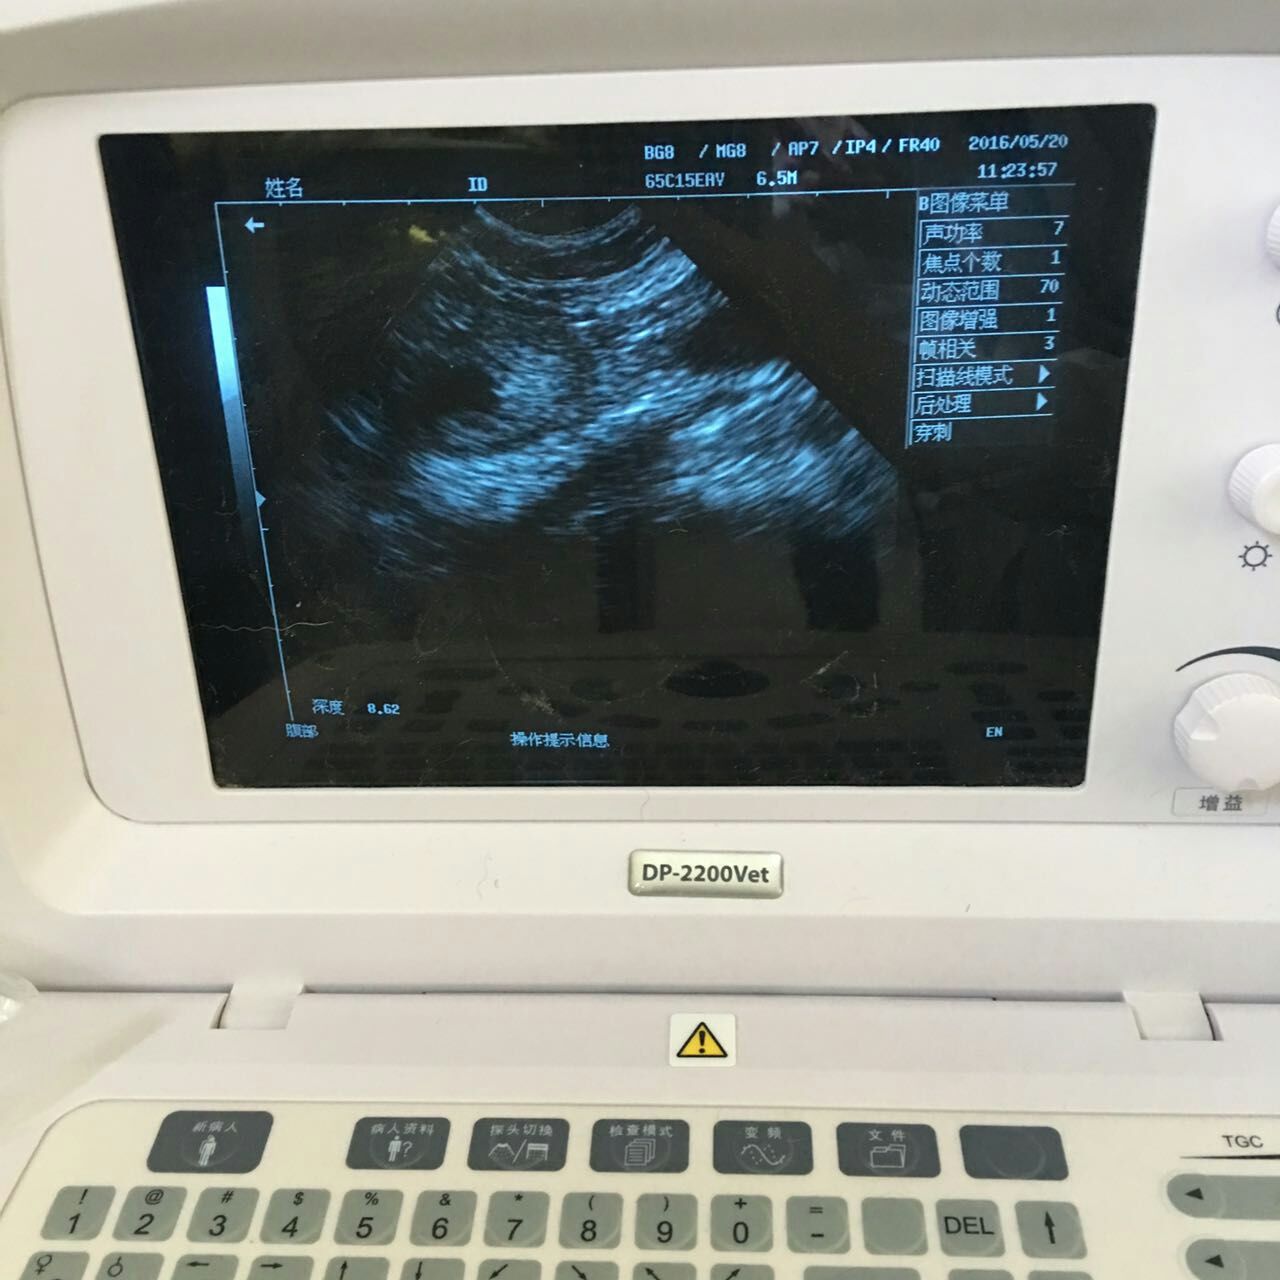

比熊犬,丑丑,雄性,3岁多。2016年5月16日,主人因丑丑尿血带来检查,检查后发现膀胱粘膜增厚,前列腺增大、囊肿。保守治疗两天后,未见明显好转,与主人沟通后,采取B超引导穿刺前列腺囊肿,抽取囊液,并行去势术,术后常规消炎7天。半月后复查,B超未探及囊肿,前列腺萎缩。小便正常,食欲精神正常。